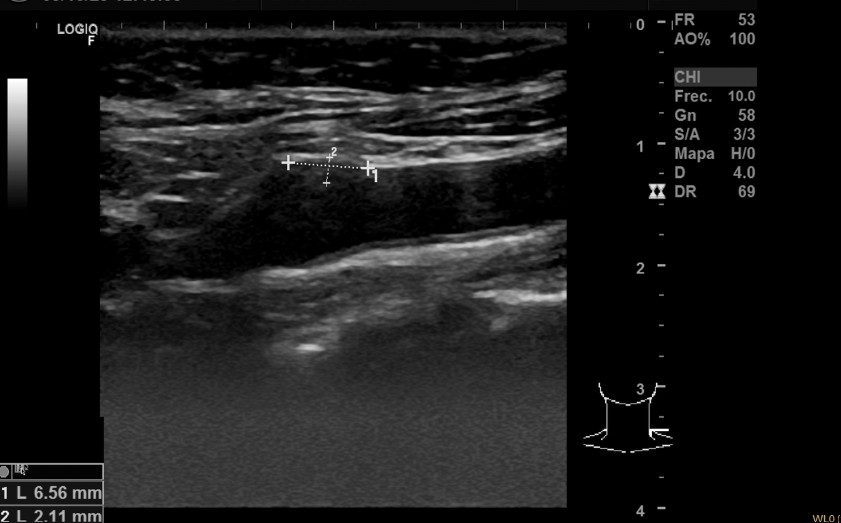

Descripción de los hallazgos ecográficos y las imágenes más relevantes para la resolución del caso: Ecografía multivaso: Placa translúcida de 1,97 x 8 mm en bulbo de carótida derecha, placa translúcida de 6,56 x 2,11 mm en carótida izquierda, placa hiperecogénica de 7,7 x 3,12 mm en femoral derecha. Aorta normal.